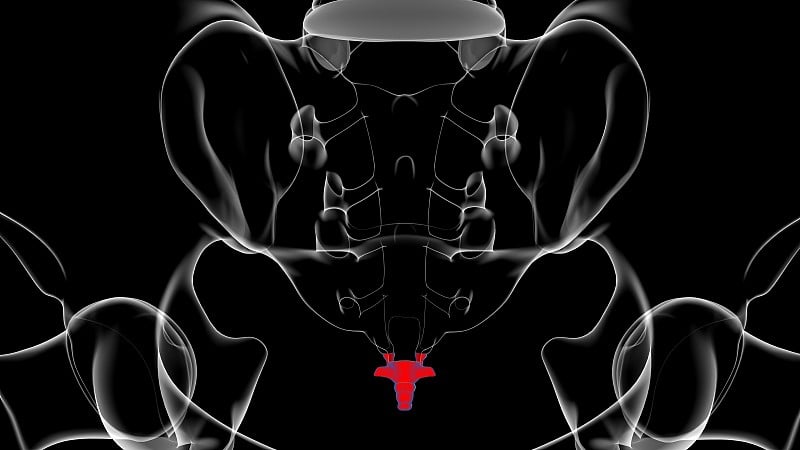

正常血管和动静脉畸形详情

EPS